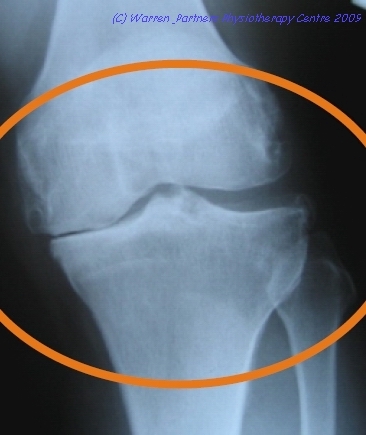

骨關節炎是一種普遍的關節疾病,是一種關節退化的現象,當膝部患上骨關節炎,會逐步出結構變化(圖二),包括:

(一) 膝關節軟骨磨損

(二) 膝關節空間收窄

(三) 軟骨下的硬骨受磨損

(四) 骨質增生(俗稱骨剌)

(五) 膝關節外觀腫大、變形